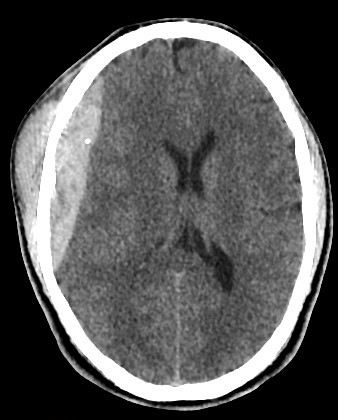

Right Fronto-Parietal

History

30 years old male with trauma